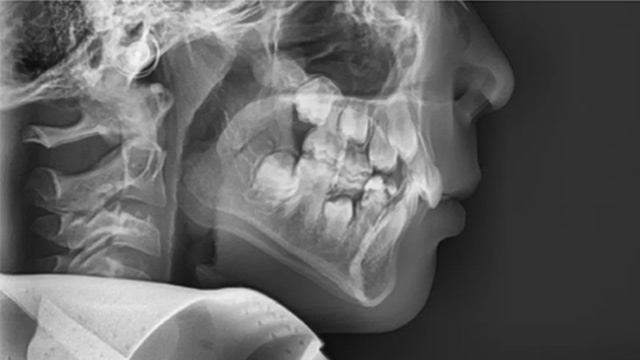

晴晴的口腔侧位片(有深覆合,无下巴后缩)